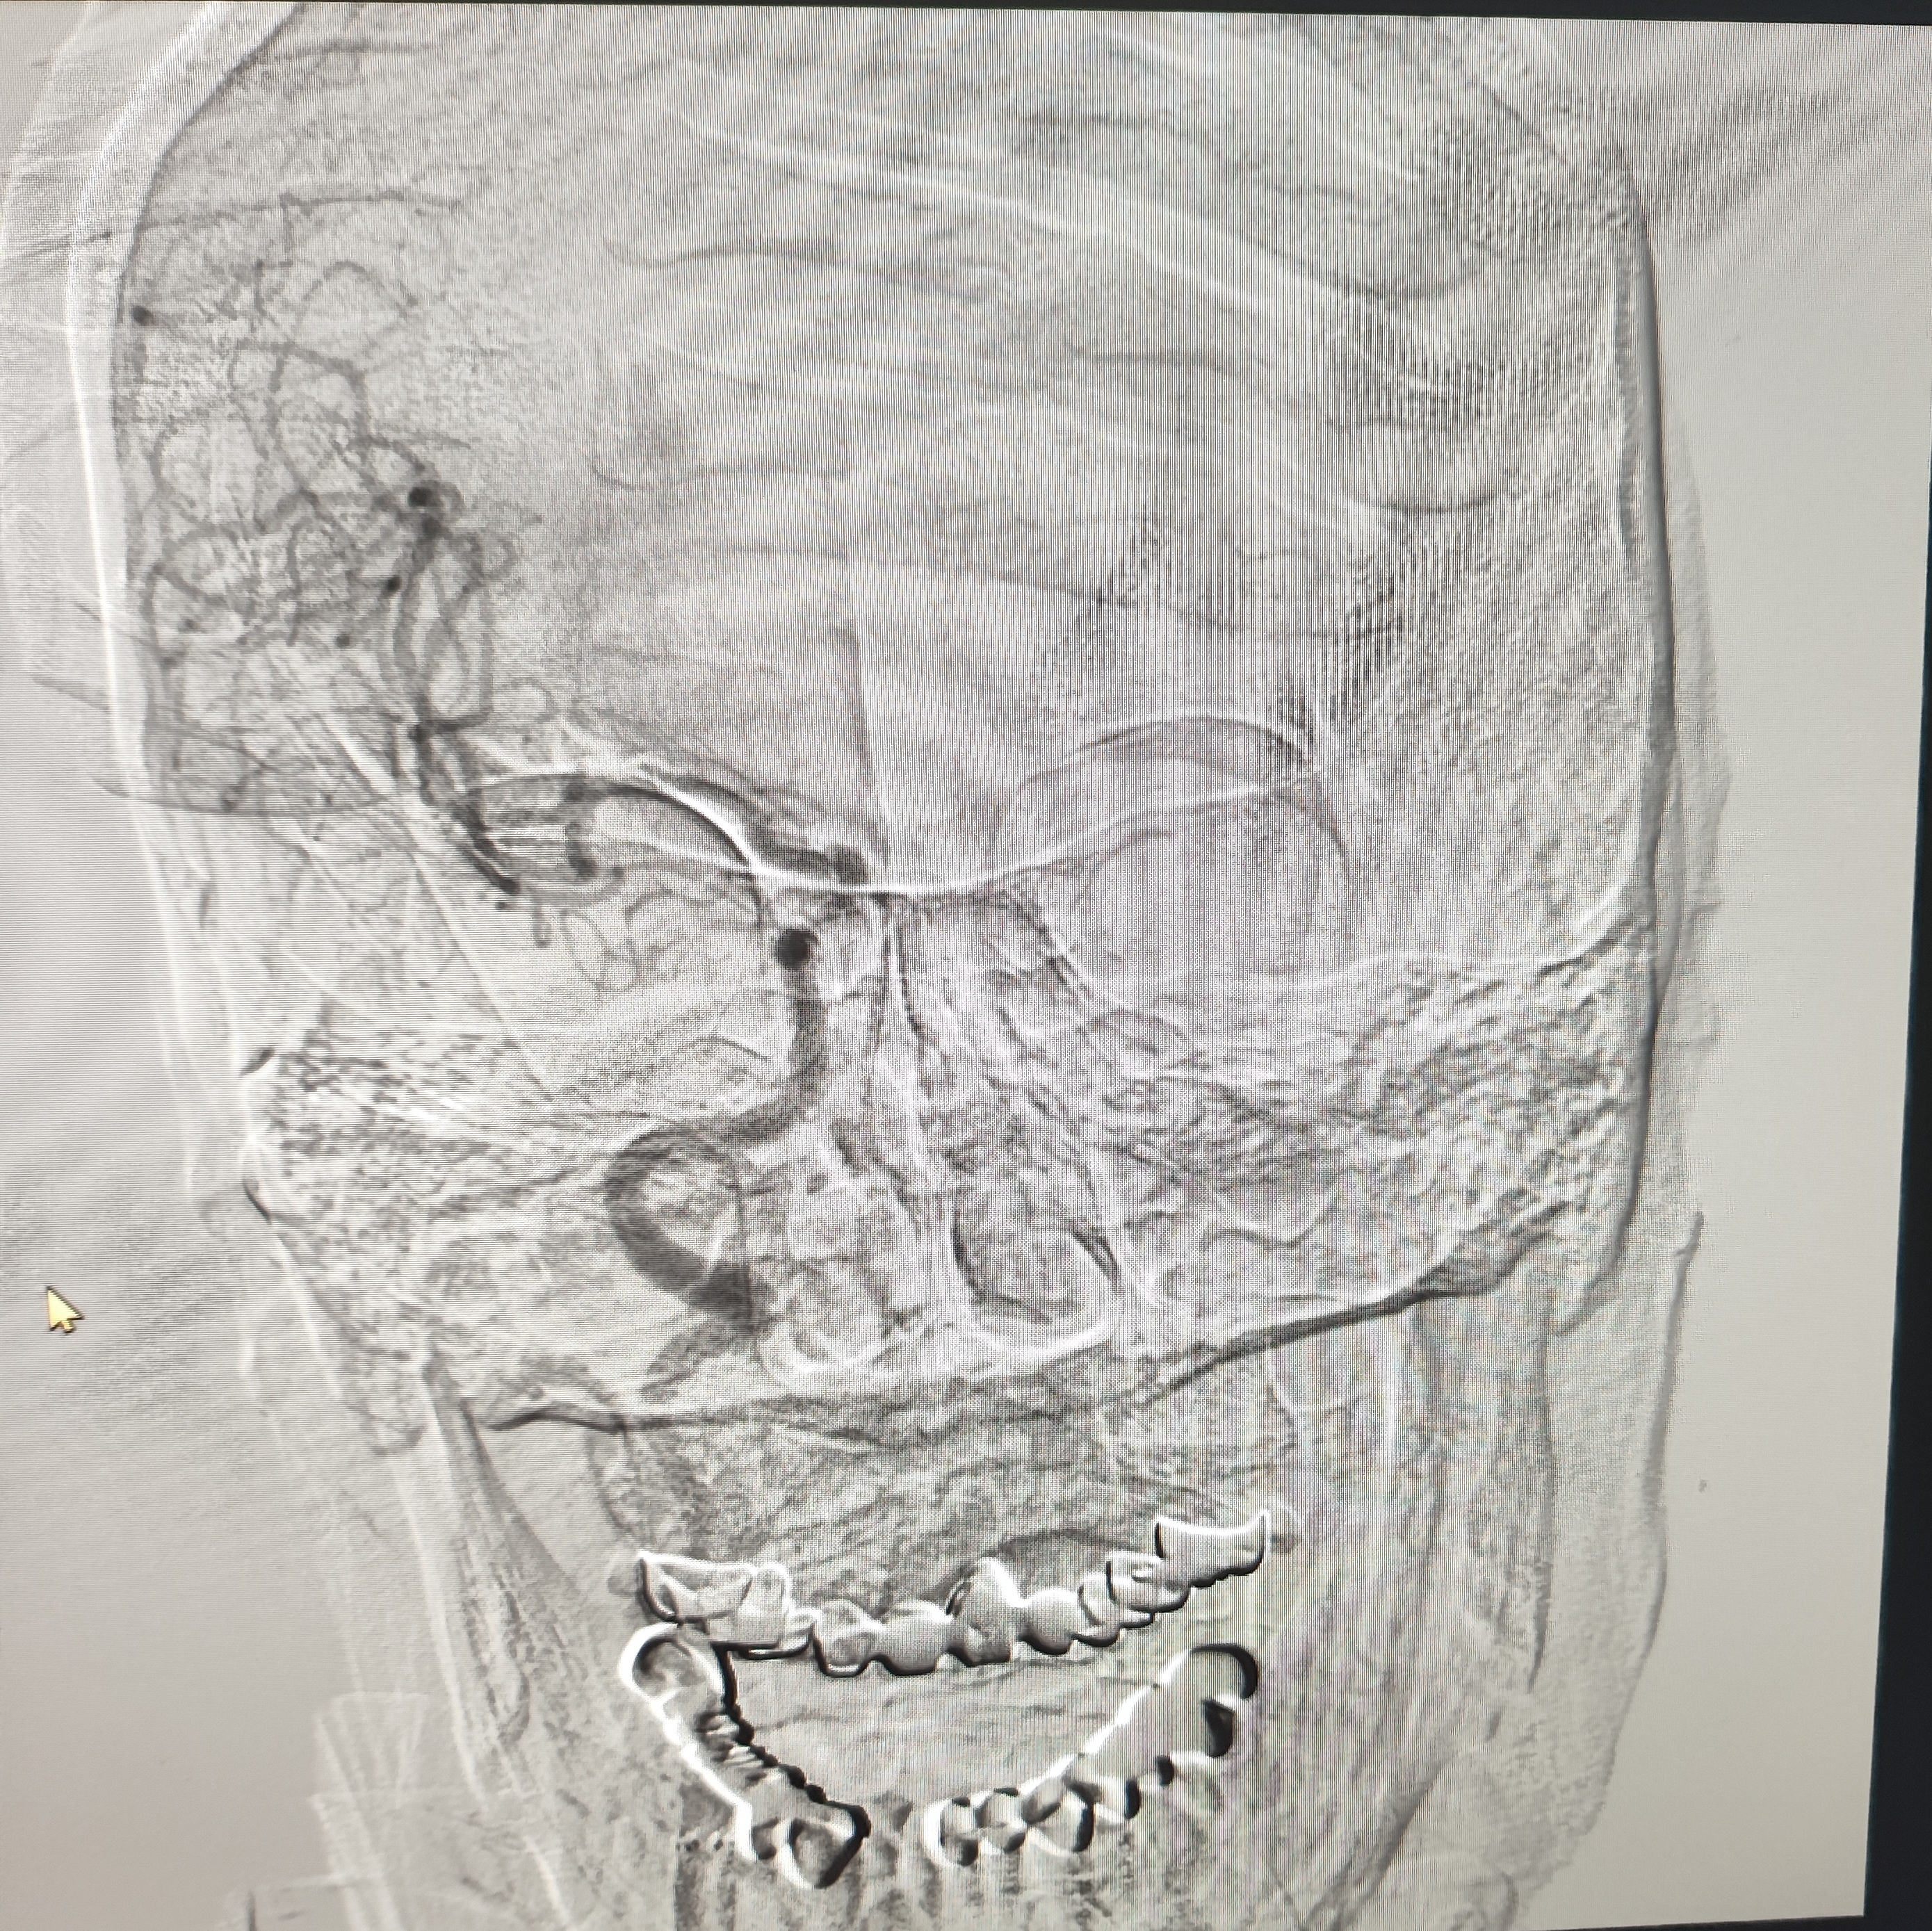

颈总巨大斑块急性闭塞的血管内治疗(双颈动脉支架桥接+支架释放后掉斑块,抽吸取栓)

84岁男性,既往右侧颈动脉狭窄病史8个月,多次脑梗未治疗,本次突发左侧肢体无力来诊,发病30小时后转入我院。

发病当日患者精神差,左侧肢体肌力4级,言语不清晰,左侧鼻唇沟略浅。

症状进行性加重,意识逐渐模糊,烦躁,左上肢肌力1级,左下肢肌力2级,当地考虑开通难度大,转入我院。

急诊上台。